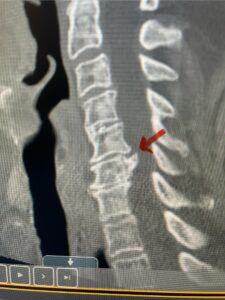

Another patient, a 77 year-old female, presents with pain, numbness, and weakness of her arms and difficulty with balance over a 6-month period. MRI revealed severe osteophytic disease at C5-C7 with cord compression (Fig. 4). Further work-up by fine-cut cervical CT to evaluate the nature of compression revealed a completely calcified osteophyte (Fig. 5). Although the patient had a good lordosis and a posterior cervical approach would accomplish an adequate decompression, we elected to perform a two-level anterior cervical discectomy and fusion. This particular osteophyte is formidable because of its size but the compression was all anterior and would be a less invasive approach. Fortunately, during the procedure, the patient had a fair amount of osteoporosis which allowed the osteophyte to be drilled and bit away with considerable ease. Interestingly, the C6 7 osteophyte which was more a sheet of osteophyte was more challenging to remove. In the end the decompression went well, and we placed two interbody devices filled with bone graft with plates at each level (Fig. 6). The patient had a nice recovery with immediate reduction of pain and numbness. This case demonstrates the importance of recognition of cervical myelopathy in its early stages. A significant reversal of function is generally the rule if the patient has appropriate correlative findings on exam and MRI, particularly with long tract distribution weakness development within a year time period.

Fig 5a: Sagittal and axial cervical fine-cut CT scan demonstrating severe osteophyte formation causing cord compression at C 56 (red arrow)

Fig 5b: Sagittal and axial cervical fine-cut CT scan demonstrating severe osteophyte formation causing cord compression at C 56 (red arrow)